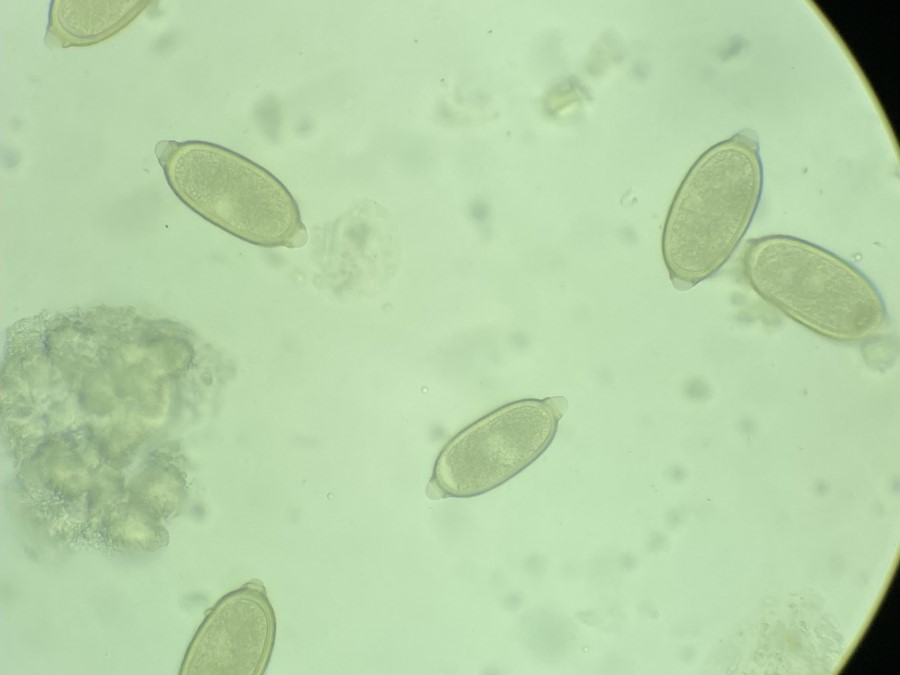

Vista 2 Nematodo gastrointestinal

Nematodo gastrointestinal

Datos taxonómicos

Género:

Capillaria

Especie:

spp

Nombre común: